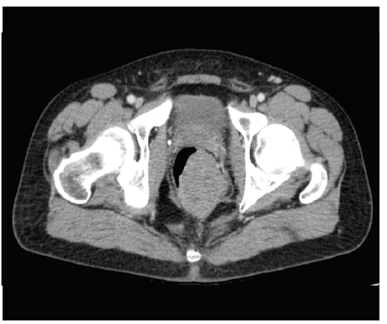

Ante estos hallazgos, se practicó una tomografía computadorizada (TC) abdominal en la que se observó una masa rectal de 73 x 62 x 48 mm (figura 1), sin demostrar una clara afectación de la grasa perirrectal, y sin que se identificara un plano graso de separación del suelo prostático. No se observaron ganglios linfáticos sospechosos.